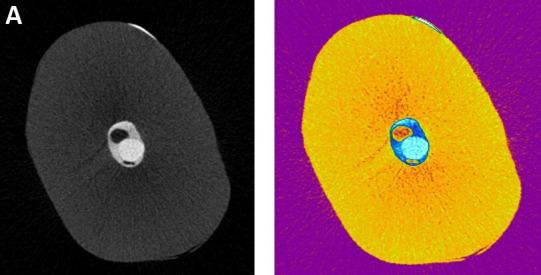

Micro-CT evaluation of the presence of voids in endodontic obturation.

Identifying the presence, size, type and location of voids in an endodontic obturation is of great clinical importance because it enables evaluation of the three-dimensionality of the sealing techniques, which can be related to the success of the endodontic treatment.

To analyze by micro-CT the presence of voids in lower single-rooted premolar root canal obturations prepared using the single cone and ultrasound vibration technique.

Twenty extracted single-rooted lower premolars were selected, and the root canal prepared surgically and chemically. In GROUP 1 - Without Vibration, the canal was obturated with a single cone and bioceramic, without applying vibration. In GROUP 2 - With Vibration, the gutta-percha cone inside the root canal was held with a cotton plier to which ultrasound vibration was applied for 3 periods of 3 seconds each. A micro-CT scanner was used to acquire and reconstruct images for analysis.

No significant difference was found between obturation techniques, though there were differences between thirds, with the cervical third having a higher percentage of voids than the middle and apical thirds.

The results suggest that the volume of closed, open and total voids does not differ between treatments with and without ultrasound vibration. In the cervical third, the highest volume of voids was related to oval geometry in the teeth evaluated.